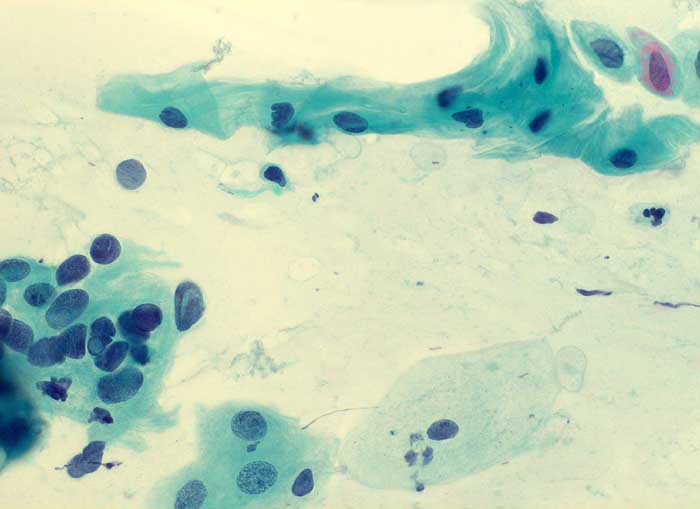

g/ Nicht klassifizierbare Plattenepithelien (ASCUS)

Nicht klassifizierbare Plattenepithelien (ASCUS)

Die Kategorie "atypical squamous cells of undetermined significance" der Bethesda Klassifikation umfasst entzündliche, reaktive und nicht klassifizierbare Plattenepithelveränderungen. Die Atypien übersteigen dabei das Mass gewöhnlicher reparativer Veränderungen. In den meisten Fällen sind reife Plattenepithelien betroffen. Nicht klassifizierbare Plattenepithelveränderungen können aber auch in metaplastischen oder atrophen Epithelien angetroffen werden. Die Diagnose ASCUS im atrophen Abstrich kann dann gestellt werden, wenn die Kerne mindestens zweimal so gross sind wie normal und eine deutliche Hyperchromasie zeigen, die Kernkontur bzw. Chromatinverteilung unregelmässig ist oder eine deutliche Pleomorphie in Form von Tadpole Zellen oder spindeligen Zellen vorhanden ist. In solchen Fällen kann nach einer kurzfristigen lokalen Östrogenbehandlung der Abstrich wiederholt werden. Gutartige atrophieassoziierte Veränderungen verschwinden unter Östrogentherapie. Signifikante präkanzeröse Läsionen persistieren hingegen und sind auf dem Hintergrund ausgereifter Zellen besser erkennbar.